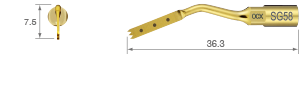

Escisiones en áreas con planos inclinados o proyecciones, o de difícil acceso con punta SG1 u otras puntas normales.

• POTENCIA [SURG] 80%

• Revestimiento de TiN

• Punta con curva a la derecha*

• Tres dientes; 0,6 mm de grosor

* La dirección del ángulo de la punta viene definida por la vista anterior de la punta.

Escisiones en áreas con planos inclinados o proyecciones, o de difícil acceso con punta SG1 u otras puntas normales.

• POTENCIA [SURG] 80%

• Revestimiento de TiN

• Punta con curva a la izquierda*

• Tres dientes; 0,6 mm de grosor

* La dirección del ángulo de la punta viene definida por la vista anterior de la punta.